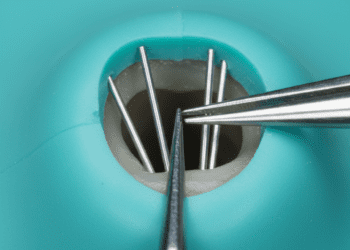

Quando a recessão alcança níveis significativos, procedimentos cirúrgicos podem ser necessários para restaurar a margem gengival. Entre as técnicas mais comuns, destacam-se:

- Enxerto gengival livre: Consiste na retirada de tecido gengival da região do palato para cobertura da raiz exposta.

- Enxerto de tecido conjuntivo: Técnica que utiliza uma camada do tecido abaixo da gengiva do palato para recobrir a área afetada, favorecendo a cicatrização e a formação de nova gengiva.

- Retalho gengival: Levantamento da gengiva local para reposicionamento e melhor cobertura da raiz.

- Uso de membranas ou substitutos gengivais: Em alguns casos, materiais biocompatíveis são aplicados para auxiliar na regeneração dos tecidos.